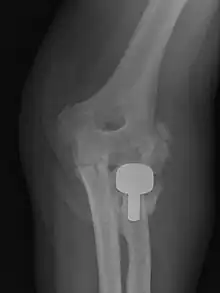

| Heterotopic ossification around the hip joint in a patient who has undergone hip arthroplasty |

Heterotopic ossification of varying severity can be caused by surgery or trauma to the hips and legs. About every third patient who has total hip arthroplasty (joint replacement) or a severe fracture of the long bones of the lower leg will develop heterotopic ossification, but is uncommonly symptomatic. Between 50% and 90% of patients who developed heterotopic ossification following a previous hip arthroplasty will develop additional heterotopic ossification.